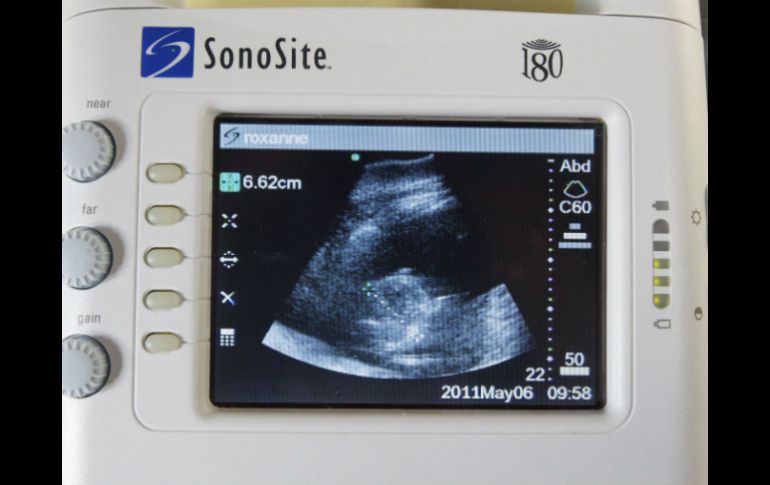

Tecnología | Este tipo de estudios podrían servir para evitar exposición innecesaria a la radiación Ultrasonidos y tomografías, eficientes para hallar piedras renales Este tipo de estudios podrían servir para evitar exposición innecesaria a la radiación Por: AFP 17 de septiembre de 2014 - 20:27 hs Con el ultrasonido se evita la exposición a la radiación sin que aumenten las consecuencias negativas. EFE ARCHIVO. / WASHINGTON, ESTADOS UNIDOS (17/SEP/2014).- Los estudios de ultrasonido son igual de eficientes que las tomografías computarizadas para hallar piedras renales y deberían ser usados con este fin para evitar una exposición innecesaria a la radiación, dijeron investigadores el miércoles. El trabajo publicado en la revista científica New England Journal of Medicine se basó en el estudio de tres mil personas tomadas al azar de salas de emergencia que presentaban síntomas de cálculo renal. Algunos fueron examinados con ultrasonido por un doctor de la emergencia, otros con ultrasonido por un médico especializado y otros fueron sometidos a una tomografía computarizada por parte de un radiólogo. Tras seis meses de seguimiento, los autores del estudio no constataron ninguna diferencia en el estado de salud de los pacientes, independientemente de la técnica usada por el especialista para su diagnóstico. En Estados Unidos, las tomografías se usan con mucha más frecuencia que los ultrasonidos cuando un paciente presenta síntomas de dolor que sugieren una cálculo renal. Pero este estudio urgió a los doctores a detener esta sobreabundancia de tomografías y a efectuar los análisis iniciales siempre con un ultrasonido. Con el ultrasonido, "se evita la exposición a la radiación sin que aumenten las consecuencias negativas en ningún sentido y sin aumento en los costos", dijo la autora líder de la investigación, Rebecca Smith-Bindman, profesora de la Universidad de California en San Francisco. Temas Estudios Enfermedades Calor de hogar Lee También ¡Toma nota! 5 razones para lavar los trastes en casa con sal ¿Cómo quitar el mal olor de los zapatos de manera natural? ¿Cómo secar rápido la ropa y evitar malos olores en temporada de lluvias? Esclerosis: Qué es y cuáles son los daños que deja la enfermedad Recibe las últimas noticias en tu e-mail Todo lo que necesitas saber para comenzar tu día Registrarse implica aceptar los Términos y Condiciones